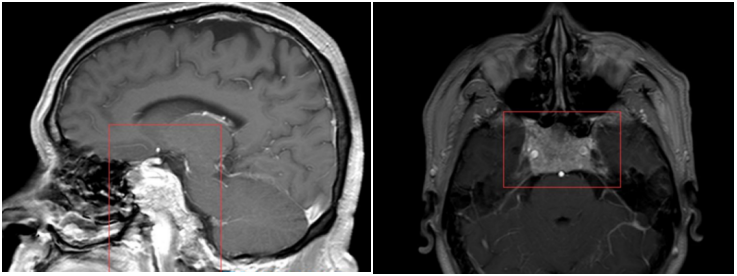

图1:术前MRI斜坡区占位,包绕颈内动脉大动脉及视神经,并压迫脑干

李先生的肿瘤位于上斜坡并占据全部中斜坡区域,将中脑、脑桥向后压迫,向外侧延展累及双侧颈动脉,手术难度非常大。